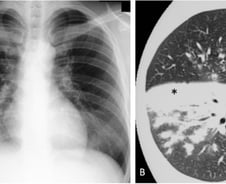

중국을 휩쓴 마이코플라스마(마이코플라즈마) 폐렴균 감염증이 국내에서도 빠르게 확산하고 있다. 최근 4주간 감염자가 2배(10월 셋째 주 102명→ 11월 둘째 주 226명)나 증가했다. 특히 국내 환자 10명 중 8명이 '12세 이하' 어린이라는 점에서 학부모들이 긴장하고 있다. 게다가 증상이 감기와 비슷해 초기 진화를 못 할 가능성이 큰 데다, 독감·코로나19와 동시다발적으로 걸리면 위중증으로 나빠질 수 있어 주의해야 한다. 과연 마이코플라스마 폐렴균 감염증(이하 마이코플라스마 폐렴)이 뭐고, 증상은 감기와 어떻게 다를까? 마이코플라스마 폐렴은 마이코플라스마 폐렴균(Mycoplasma pneumoniae)으로 발생하는 급성 호흡기 감염증으로, 우리나라에선 법정 감염병(제4급)으로 관리한다. 이 균에 감염된 사람의 침이 다른 사람의 호흡기로 튀거나 이동할 때 잘 감염된다. 몸속에 들어온 이 균은 평균 2~3주간 잠복했다가 증상으로 나타난다. 감기와 증상이 비슷한 듯 다르다. 감기는